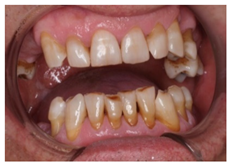

3.5. Clinical Scenario #5

In this scenario, the participants were asked to select the most adequate treatment option for the treatment of the carious lesions present in teeth 1.3, 1.2, 1.1, 2.1, 2.2, and 2.3. The most prevalent answer for teeth 1.3, 1.1, 2.1, and 2.3 (94.2%) was “remineralization” (clinical scenario 5a), which was the correct answer. For tooth 1.2 (clinical scenario 5b), the most prevalent answer was “root canal treatment” (51.2%), followed by “restoration with resin composite” (22%). For tooth 2.2 (clinical scenario 5c), the most popular option was “restoration with resin composite” (85.4%), followed by “remineralization” (22%). The correct answer for teeth 1.2 and 2.2 was “restoration with resin composite” (Figure 1).

3.9. Clinical Scenario #9

Similar to clinical scenarios 7 and 8, students were required to order different treatment alternatives for the proposed case. A total of 43.9% of the students would “replace the restoration in its integrity with a new direct restoration”, 39% would “replace the restoration with an incrustation”, and 12.2% would “replace the restoration partially and restore the anatomy of the tooth”. This last option was considered as correct (Figure 1).

Currently, there is a great tendency towards the restoration of lesions limited to the enamel, although the scientific evidence supports other non-invasive alternatives for the control of these lesions [35]. According to these criteria, an inactive carious lesion categorized as ICDAS II (clinical scenario 1c) should not receive any restorative treatment, but only require oral health instructions and control of individual risk factors, together with follow-up control visits [35]. Interestingly, the percentage of students who correctly answered the therapeutic approach in scenario 1c (51.2%) was higher than those who correctly answered the diagnosis in scenario 1a (48.8%). This difference may have been due to the fact that students who misdiagnosed scenario 1a as “healthy” or “early carious lesion” may have selected “oral health instructions and 6-month follow-up visit” as a therapeutic approach. However, a little more than half of the students selected this non-invasive therapeutic alternative. It should be highlighted that up to 41.7% of the students would place a resin composite restoration, which in this case is considered as an “overtreatment”. Available systematic reviews among the literature regarding the treatment for early carious lesions found a significative proportion of dentists who would propose restorative treatments upon carious lesions for which minimally invasive technique are indicated [30,32]. Thus, it is necessary to orient dental students into a less invasive approach, taking into account the natural progression of the disease, and treating lesions according to their extension and carioactivity. Because the influence of the type of undergraduate formation influences the postgraduate therapeutic attitude [36].

The majority of students coincided with the available protocols for approaching active carious lesions limited to enamel (clinical scenario 5a). However, when lesions extended to dentin (clinical scenarios 5b and c), the therapeutic alternatives were more discordant. Specifically, for the treatment of tooth 1.2, in which the extension of the carious lesion surpassed the external third of the dentin, 51.2% of the students proposed a root canal treatment, which is considered as an overtreatment in this case [35].

The replacement or repair of defective restorations are common techniques among daily dental practice [24]. In a clinical study by Moncada G. et al., the effectiveness of different therapeutic approaches for the treatment of defective restorations was evaluated for 3 years. The authors observed that, by replacing the defective restoration in its integrity, no greater durability was achieved when compared to a more conservative approach, i.e., repairing the defective restoration [41]. Only 12.2% of the surveyed students would have opted for the repair of the defective restoration presented in clinical scenario 9. The rest of the participants selected the option involving the complete replacement of the defective restoration or the placement of an incrustation. Both options could be performed and can be adequate from a technical point of view, but would not be as conservative [24].